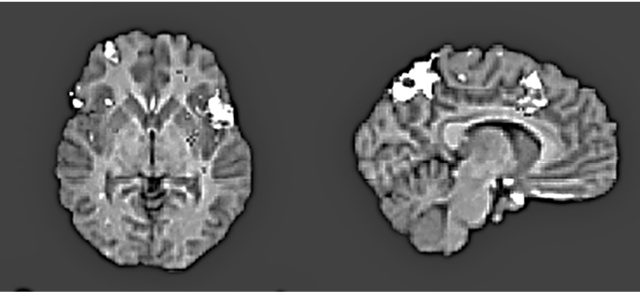

Но это было еще не все. Харрис обнаружил, что оценка «верю» сопровождалась усилением активности в вентромедиальной префронтальной коре (рис. 8.1a ниже) – участке мозга, отвечающем за совмещение факта и эмоции и изменение поведения в ответ на изменение обстоятельств (другими словами, уравновешивание «за» и «против»). «Не верю», в свою очередь, активизировала переднюю островковую долю мозга (рис. 8.1b) – участвующую в том числе и в кодировании негативных реакций, таких как боль и отвращение, и в оценке приятности различных вкусов и ароматов.

Рис. 8.1b. Осевое изображение (слева) показывает повышенную активность в нижней лобной извилине (в основном слева), в средней лобной извилине справа и в области островка с обеих сторон при оценке ложных утверждений по семи разным тематическим категориям. Изображение, напоминающее стрелку (справа), показывает повышение активности в верхней теменной доле, поясной коре и верхней лобной извилине (по материалам Харриса и др., 2008)